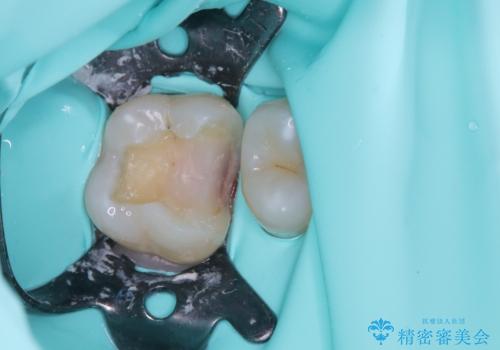

拡大鏡下で、銀歯、むし歯の除去を行い、セラミックインレーに適した形に整えました。

精度の良いインレーを製作するために、シリコーンにて型どりしました。

また確実な接着操作を行うために、インレーを接着する際にはラバーダム防湿を行いました。